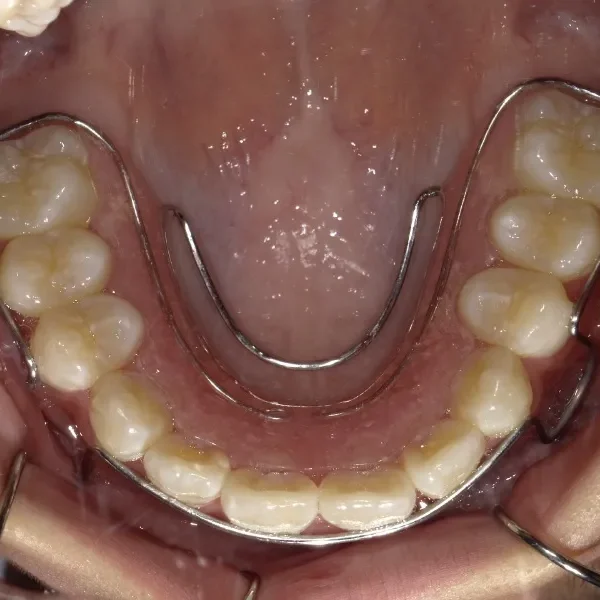

下の歯がずれて生えています。

こどもの歯は下の2本しか抜けていませんが、放っておくとガタガタがきつくなるので、早い段階からの治療としました。

初診